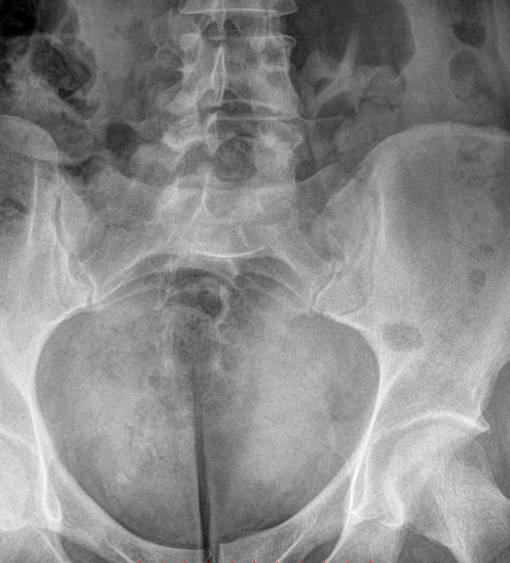

Рентгенографическое исследование при болях в нижней части спины хорошо визуализирует состояние костной ткани, дает возможность подтвердить диагноз и назначить наиболее эффективное лечение. Снимки выполняются в 2 проекциях: прямой и боковой. На рентгенограмму обычно попадают: 5-й поясничный позвонок, крестец и копчик. В прямой проекции также видны крестцово-подвздошные суставы.

• Изменения в крестцово-подвздошных сочленениях ― контуры, рентгеновская суставная щель;